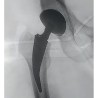

hip prosthesis

Sale of new generation hip prosthesis in Tunisia also called hip endoprosthesis at a good quality and price ratio. The high-quality Universal Hip Prosthesis allows orthopedic surgeons to implant cemented or uncemented straight-stem prostheses.

The hip prosthesis admits modern technical characteristics in orthopedic surgery, the choice of your good prosthesis is made by the orthopedist. Standardized implant techniques are available for different femoral anatomy. The hip implant is also suitable when the medullary cavity is narrowed.

Characterized by the universal system for all hip prosthesis indications. Special instruments such as bone profilometers ensure maximum preservation of cancellous bone in the proximal femur.